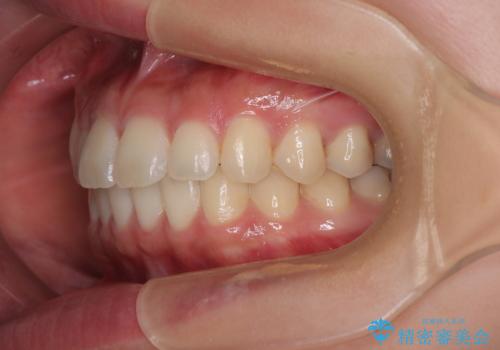

- 上下前歯のデコボコを気にして来院された患者様です。

ワイヤー矯正でもマウスピース矯正でも可能でしたが、短期間で、自身の手を煩わせることなく治療を行いたいとのことで、ワイヤー装置にて矯正治療を行うこととしました。

僅か8ヶ月という短期間で、綺麗な歯列に仕上がりました。